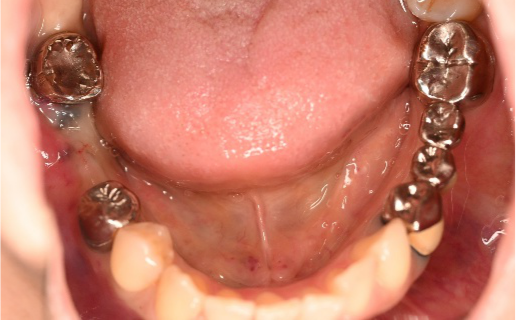

男性 Kさん 60代 (インプラント)

主訴

下の左右歯がないところに歯を入れたい。

治療内容

左右それぞれ3本歯がないところに2本ずつインプラントを埋入しました。

所感

上と下の歯の咬合接触がないすれ違い咬合です。上下義歯で対応するには最も難しいタイプの欠損状況です。治療開始前は、上下部分入れ歯が入っていましたが、入れ歯の安定が悪く、あちこちの歯茎に入れ歯が当たって痛く、満足に噛める状態ではありませんでした。上顎は、残ってる歯を活用するマグネット式総義歯を、下顎はインプラントを提案しました。上顎は、現在残っている歯の根管治療中です。上顎にマグネット式総義歯がはいれば、何でも食べられるようになります。

インプラント4本:¥363,000×4本=¥1,452,000(税込)

ポンティック2本:¥115,500×2本=¥231,000(税込)

合計:¥1,683,000(税込)

Before

▼初診時に使用していた部分入れ歯を装着したところ

▼インプラント埋入前

After

▼インプラント埋入後